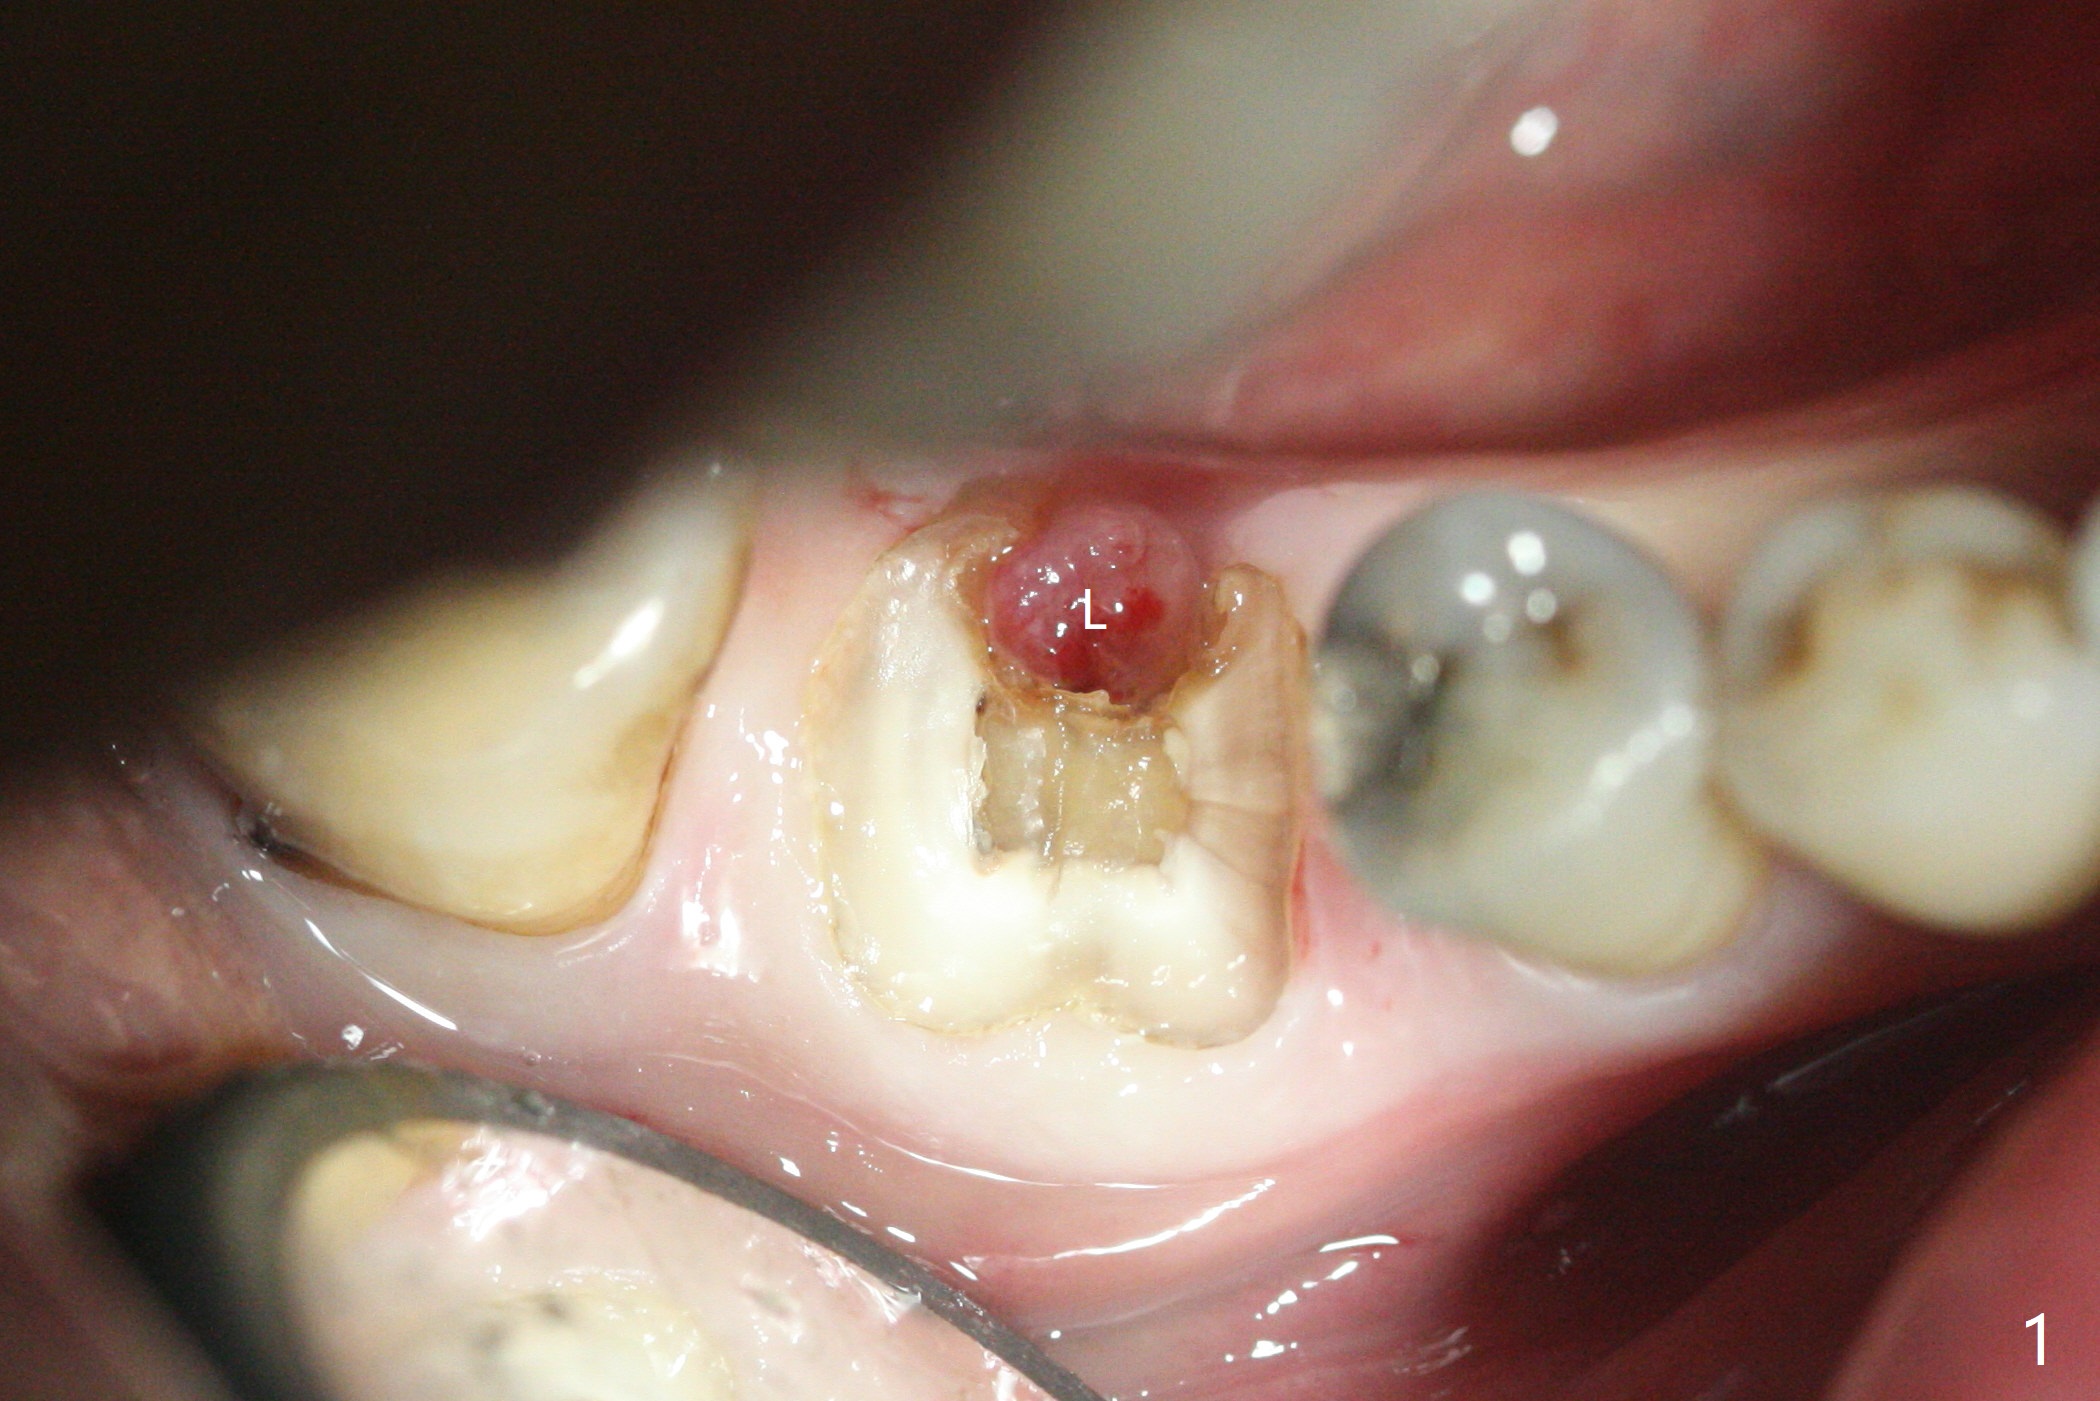

As planned, the crown of the tooth #30 with lingual (Fig.1 L) caries is removed and flattened with surgical handpiece so that the guide is able to be seated without interference. The osteotomy by 10.5 mm offset bone trimmer is lingual (Fig.2 white circle; due to in part the lingual caries and in part design error); in order to let the osteotomy to bounce back buccal, the part of the buccal roots are removed by surgical bur (arrows). The initial osteotomy by 2.2 mm drill is in the middle of the septum (Fig.3). After the last drill (3.5x11.5), the remaining roots are easily removed with proximators; a 4x11 mm dummy implant is placed with low stability and supracrestal lingual (Fig.4). Therefore a 4.5x9 mm final implant is placed with low torque. Following 4x11.5 mm drill, the torque increases to 20 Ncm. With insertion of healing screw, sticky bone (Fig.4 *: .5-1 mm cortical/cancellous allograft) is heavily packed around the implant (arrow), which apparently allows removal of the healing screw and placement of a 6x5.7(3) mm pair abutment without loosening the underlying implant. More bone graft is placed (Fig.6), followed by 2 pieces of PRF membranes. Although the implant is slightly buccally placed (Fig.7, due to over-removal of the buccal root, Fig.2 arrows), it is placed in the septum (Fig.8 S). To further compensate for the low implant stability, setting acrylic is applied in the edentulous area, particularly into the undercuts of the neighboring teeth (Fig.9 *) and around the abutment. The lingual margin of the acrylic dressing is extended (Fig.10 arrow) to cover the soft tissue defect associated with the lingual caries. As compared to the design (4x10 mm, Fig.11), the implant (4.5x9 mm, Fig.12) is placed buccal and ~ 2 mm deeper, reducing the chance of periimplantitis. The acrylic dressing is in place, but has mobility. The gingiva is healthy 2 weeks postop. The dressing is removed 1 month postop; the socket heals around the abutment buccal (Fig.13) and lingual (Fig.14). In spite of the immediate provisional, the abutment margin is substantially subgingival mesial 4 months postop, extremely difficult to take impression. A smaller diameter and longer cuff abutment is placed (Fig.15). The lingual gingiva heals normal 5 months postop, immediately before cementation (Fig.16).